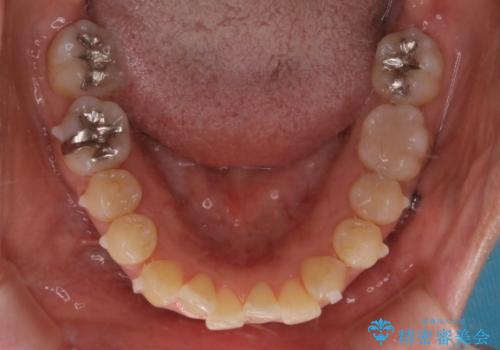

- 右上の2番目の歯が内側に入っているのと、下の前歯のがたつきが気になるとご相談にいらした方です。

上下左右の歯を後ろに動かして歯を並べるスペースを確保し、内側に入っていた歯を綺麗に並べ、前歯の中心もお顔の中心に合うようにしました。

矯正用アンカースクリューを埋入し、上下左右の歯を後ろに動かすことで歯を並べるスペースを作りました。

元々内側に倒れていた右下の奥歯は、ゴムかけを追加で行っていただくことによりしっかり起こすことが出来ました。

歯並びが綺麗になったことでモチベーションが上がり、銀歯からセラミックへのやり替えも行っております。